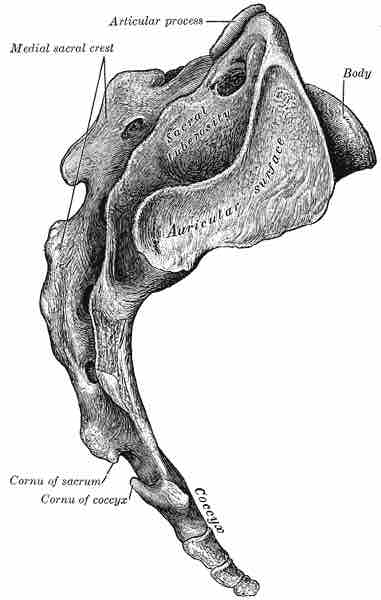

During childhood the five vertebrae of the sacral region are distinct. In adulthood the five bones fuse to form the sacrum, although it is still often divided into regions termed S1–S5 based on the formation of the original individual bones. The sacrum functions to support the body and protect organs of the pelvis and lower back.

The final region of the spine is the coccyx, or tailbone. As with the sacrum, the coccyx is formed from several vertebrae that have fused together.

As it’s alternative name suggests, the coccyx forms the basis of a tail that has been lost in humans, although it is incorrect to think of it as a vestigial structure since is a key attachment point for many muscles and ligaments and plays a key role in supporting the body while sitting.

Coccyx

Lateral view of coccyx shown beneath the sacrum.